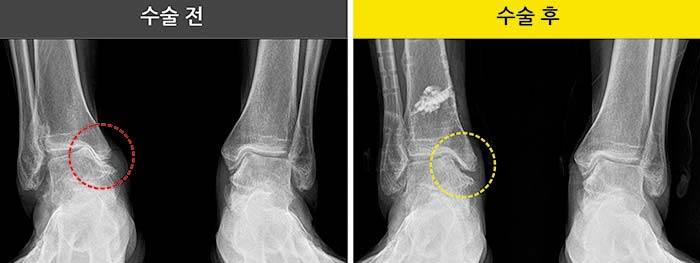

발목관절염은 1∼4기로 병기가 구분된다. 1기에는 보통 주사치료나 약물치료와 같은 보존적 치료를 시행한다. 발목내측 관절 간격이 좁아지는 2기나 내측이 무너진 3기에는 수술을 고려해야 한다. 필자의 병원은 SMO 교정술(발목과상부 경골절골술)과 내시경 연골재생술을 동시 시행해 치료의 효과를 높이고 있다. 이 술식은 자신의 발목 관절을 살리며 보존할 수 있고 회복이 빠른 장점이 있다.

SMO교정술은 내측 관절 연골에 과하게 쏠린 체중 부하축을 바깥쪽의 정상연골이 있는 외측으로 옮기는 술식이다. 발목이 다시 '정렬'이 되면 압력이 해소되어 통증이 감소하고, 수술 후 발목의 정상적 기능회복에 도움이 크다. 동시에 환자 자신의 자가골수 줄기세포를 심는 내시경 연골재생술을 시행할 수 있다. 내시경을 통해 피부절개를 최소화해 통증과 회복, 흉터 부담에 장점이 있고, 특히 표면에만 줄기세포를 도포하는 것이 아닌 연골의 깊은 곳에 줄기세포를 심어 재생된 연골의 질이 우수하다.